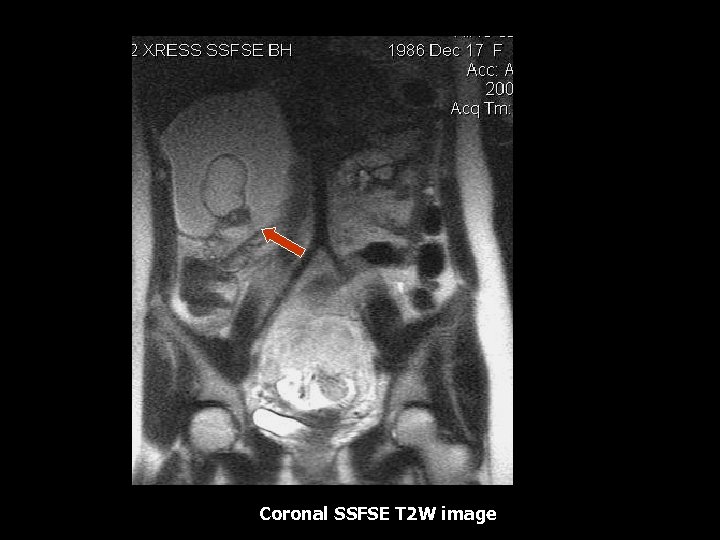

Coronal SSFSE T 2 W image

Mature Cystic Teratoma • 25 -58% of all benign ovarian tumors, 70% if age <19 (6). • Dermoids contain mesodermal, ectodermal and endodermal elements (6). • Typically an epithelial lined cyst filled with sebaceous fluid, debris and hair (6). • Intralesional mural nodule(Rockitansky nodule) is identified in >90% which may contain fat, teeth(7%)or calcifications(18%) (6). • Common complication: Torsion which occurs in 16% of cases(6). • Rare complication: Rupture(1%), Infection(1%), Autohemolytic anemia(1%), Malignant transformation(12%) (6). • Malignant transformation should be suspected if size greater than 10 cm and postmenopausal age(6).

Mature Cystic Teratoma • Characteristic MR features: Fat within the teratoma can be diagnosed with T 1 weighted, T 1 with fat suppression(2, 4). • Other MRI findings: Fat-fluid levels, dermoid nipple or mural nodule, and intracystic fat balls(7). • Calcium and bone is present will demonstrate low intensity on all pulse sequences(7).